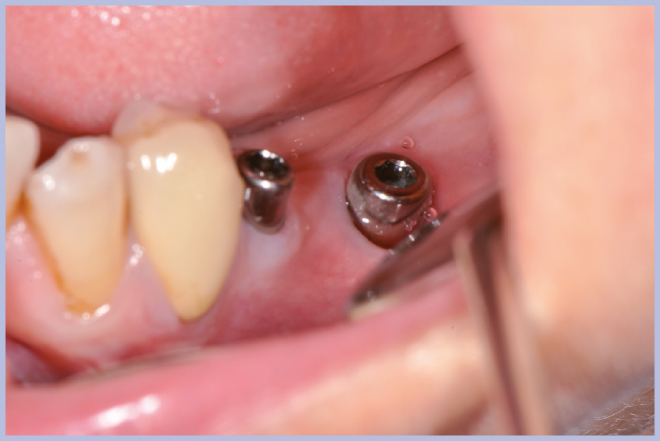

Viene quindi richiesto al tecnico di modificare in laboratorio la mascherina radiologica mediante il posizionamento delle boccole di guida adatte agli impianti da posizionare (Exacone® 6.5 e Exacone® 3,3×8) in asse con gli analoghi del modello Master 3D ed eliminando il repere radiologico standardizzato, trasformandola così nella dima chirurgica (Figg. 14, 15). Si procede quindi alla prova della mascherina sulla paziente per verificarne la stabilità e la corrispondenza esatta con il modello Master 3D (Fig. 16). La seduta chirurgica con tecnica flapless, guida chirurgica e Frese Zero1 dedicate non presenta alcuna difficoltà ; al termine dell’inserimento si posizionano sugli impianti tappi di guarigione bassi per permettere loro di guarire con tecnica sommersa (Figg. 17-27). Si effettua nella stessa seduta una CBCT che dimostra che la posizione clinica degli impianti risulta sovrapponibile a quella progettata dagli Autori (Figg. 28-30).

- Figg. 17, 18 – Passaggio dei mucotomi guidati dalla mascherina chirurgica

- Fig. 18